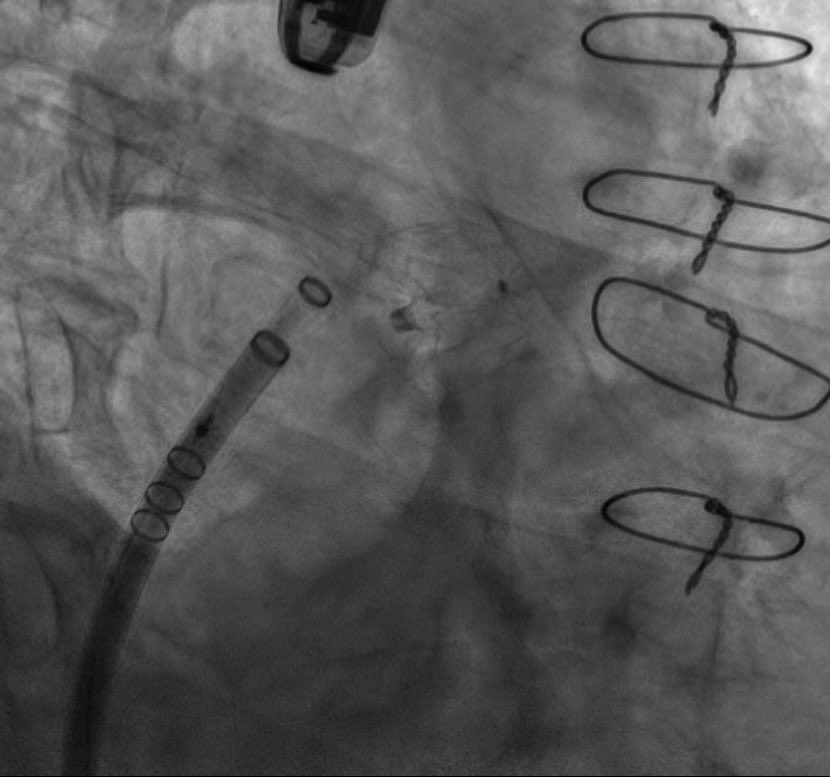

La versatilidad del dispositivo Watchman FLX permite cerrar orejuelas complejas como esta. Su pequeño tamaño supuso un reto pero finalmente conseguimos ocluirla con éxito. @GVAdsTorrevieja @CenturyRaul @bostonsci

0

11

19